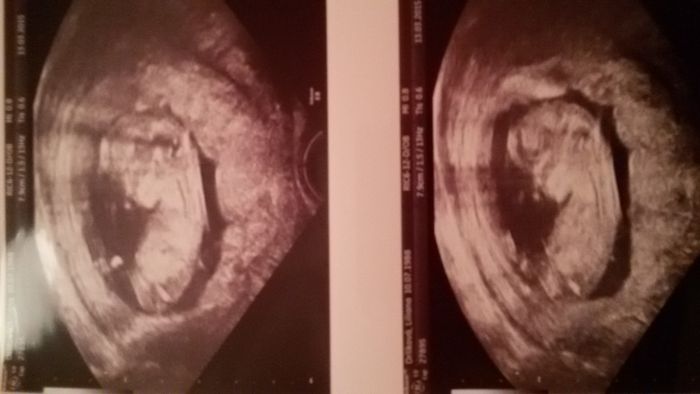

Ahoj,tak jsme konečně taky byli na screeningu,přítel nadšený konečně viděl mimi.Akorát mimi si nechtělo za žádnou cenu lehnout,tak mi to dělaly spodem,ale co se da dělat

Jinak výsledky v pořádku riziko je 1:17 358 a máme i foto, které přikládám